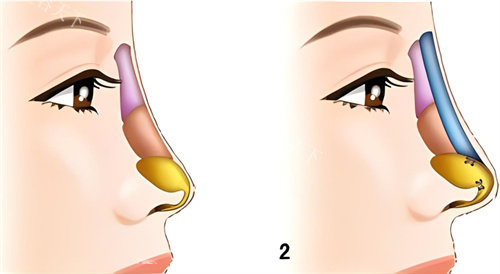

这类问题的核心在于鼻部软骨支撑力不足。传统假体隆鼻虽能垫高鼻背,但对鼻尖塑形结果有限,甚至可能因假体压迫导致鼻头更圆钝。

这也解释了为何越来越多的求美者选择半肋软骨技术——既能强化鼻梁高度,又能精细化重塑鼻尖形态。

半肋软骨技术的核心优势在于“材料源于自身,塑形更贴合原生条件”。取用肋软骨中的柔性部分雕刻鼻尖支架,既能避免假体的异物感,又能精细控制鼻尖旋转度、延长鼻小柱。

术例中的姑娘术前鼻头肥厚且皮肤张力较弱,医生特别设计了“双拱形支架”:上方用肋软骨搭建稳固的鼻梁基底,下方通过软骨颗粒填充鼻翼基底,缩小鼻头外扩的同时提升面部立体度。

解剖学精细设计:根据鼻部皮肤厚度、软骨强度定制方案,避免盲目追求高度导致鼻尖发白或穿透;

主刀医生强调:“自然鼻不是流水线产品,需要结合眉弓高度、唇形比例甚至颅骨发育来规划鼻额角。”

立体美感把控:通过鼻尖表现点、海鸥线、鼻小柱-上唇角等多维度参数塑造原生美感。